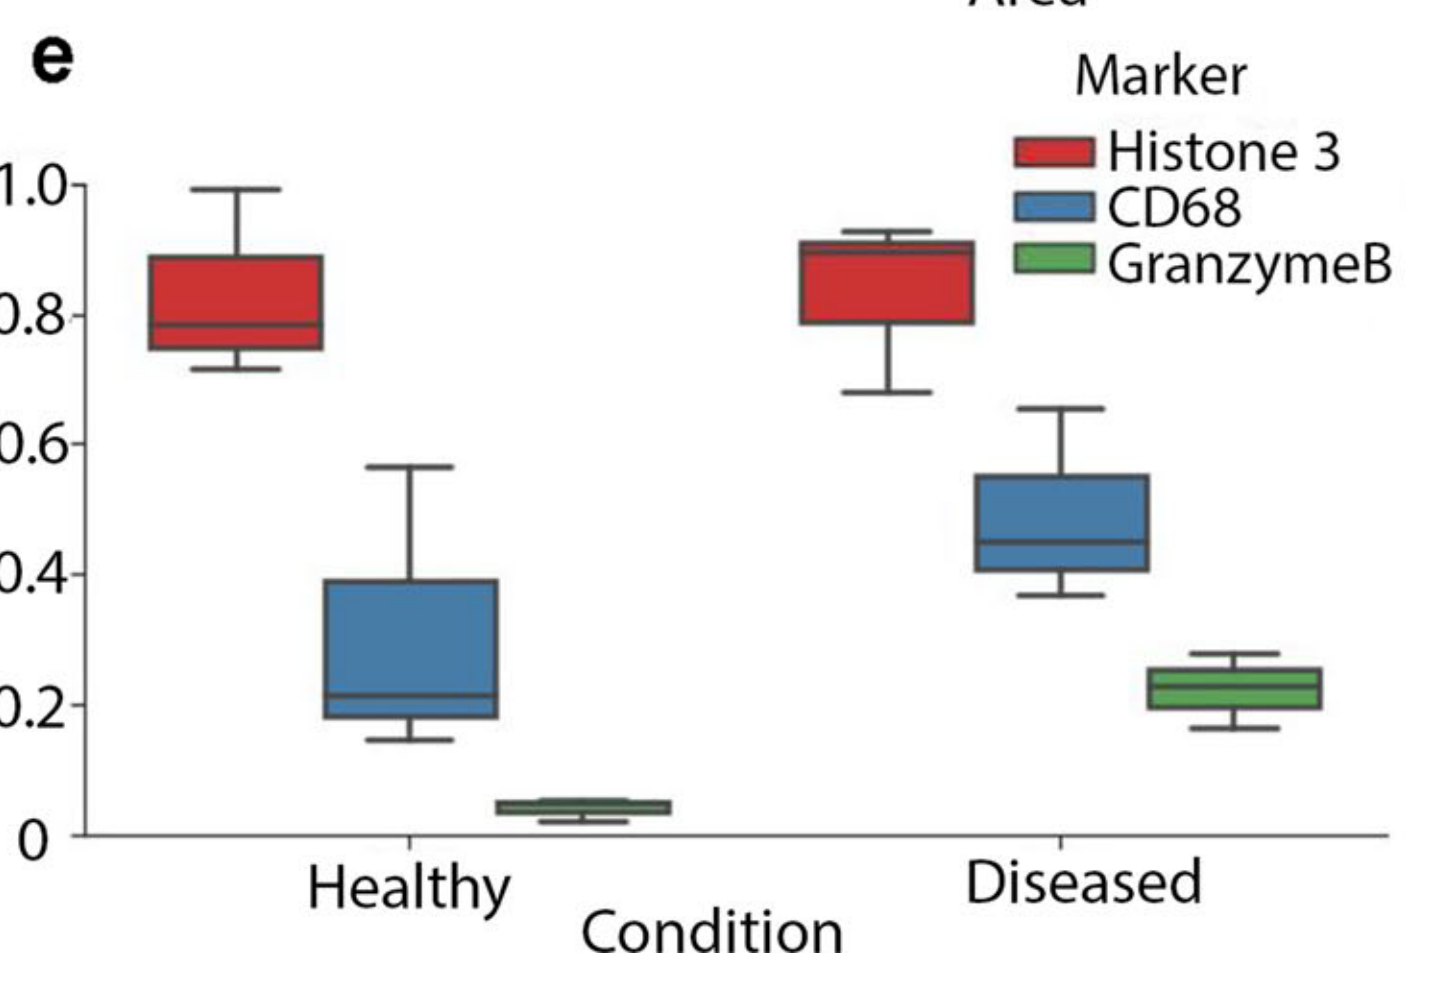

Li X. et al. - 2025

SPEX: A modular end-to-end platform for high-plex tissue spatial omics analysis

Condition Dimension

Categorical

Data Components

Biological AnnotationGene Expression Matrix

Metadata

None

Modality

Proteomics

Resolution of observation

Cellular

Visualized Elements

Statistic

How does expression of a gene differ across patient categories?

Biological

Molecular

Abstraction

Complete

Chart Type

Boxplot

Communicative/Contextualization

Annotation

Comparative Design

Juxtaposition

Layout

Linear

Scalability Strategy

Summay/Aggregate